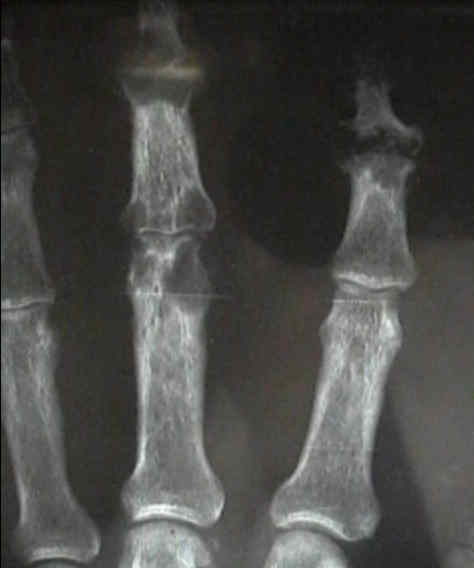

- in the hand look for oval periarticular erosions;

- multiple erosions will be distributed throughout the carpi and phalanges bilaterally;

- erosions have sclerotic borders and will often have overhanging edges;

- unlike classic RA, in early gout, hand and wrist joints will have preserved joint spaces and normal mineralization;

- example: